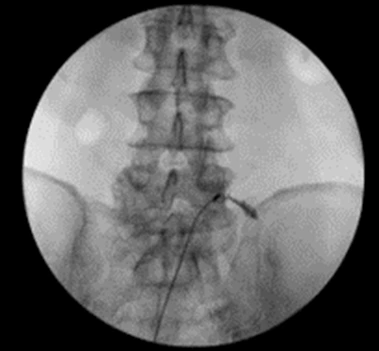

환자분도 동의하셔서 PEN 시술을 진행했어요.

PEN 시술은 꼬리뼈를 통해

가느다란 카테터를 넣어 유착된 신경을 풀어주고,

염증을 제거하는 시술이에요.

%EA%B7%B8%EB%A6%BC7.png?type=w966

[가운데를 가로지르는 가느다란 카테터 보이시죠? ^^]

시술 후 1주일 뒤 재진 때 환자분 표정이 확 밝아지셨더라고요.

"선생님, 진짜 신기해요. 발바닥 화끈거림이 확 줄었어요.

밤에도 잘 수 있게 됐고요!"

통증 척도도 처음 오셨을 때 9였는데,

4까지 떨어졌다고 하셨어요.